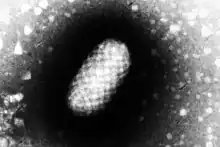

It is caused by a Parapoxvirus.[5] It can occur in humans who handle infected animals or contaminated objects.[2] One third of cases may develop erythema multiforme.[4] Once resolved, a person can still be infected again.[4]

| Genus: | Parapoxvirus |

| Species: | Orf virus |